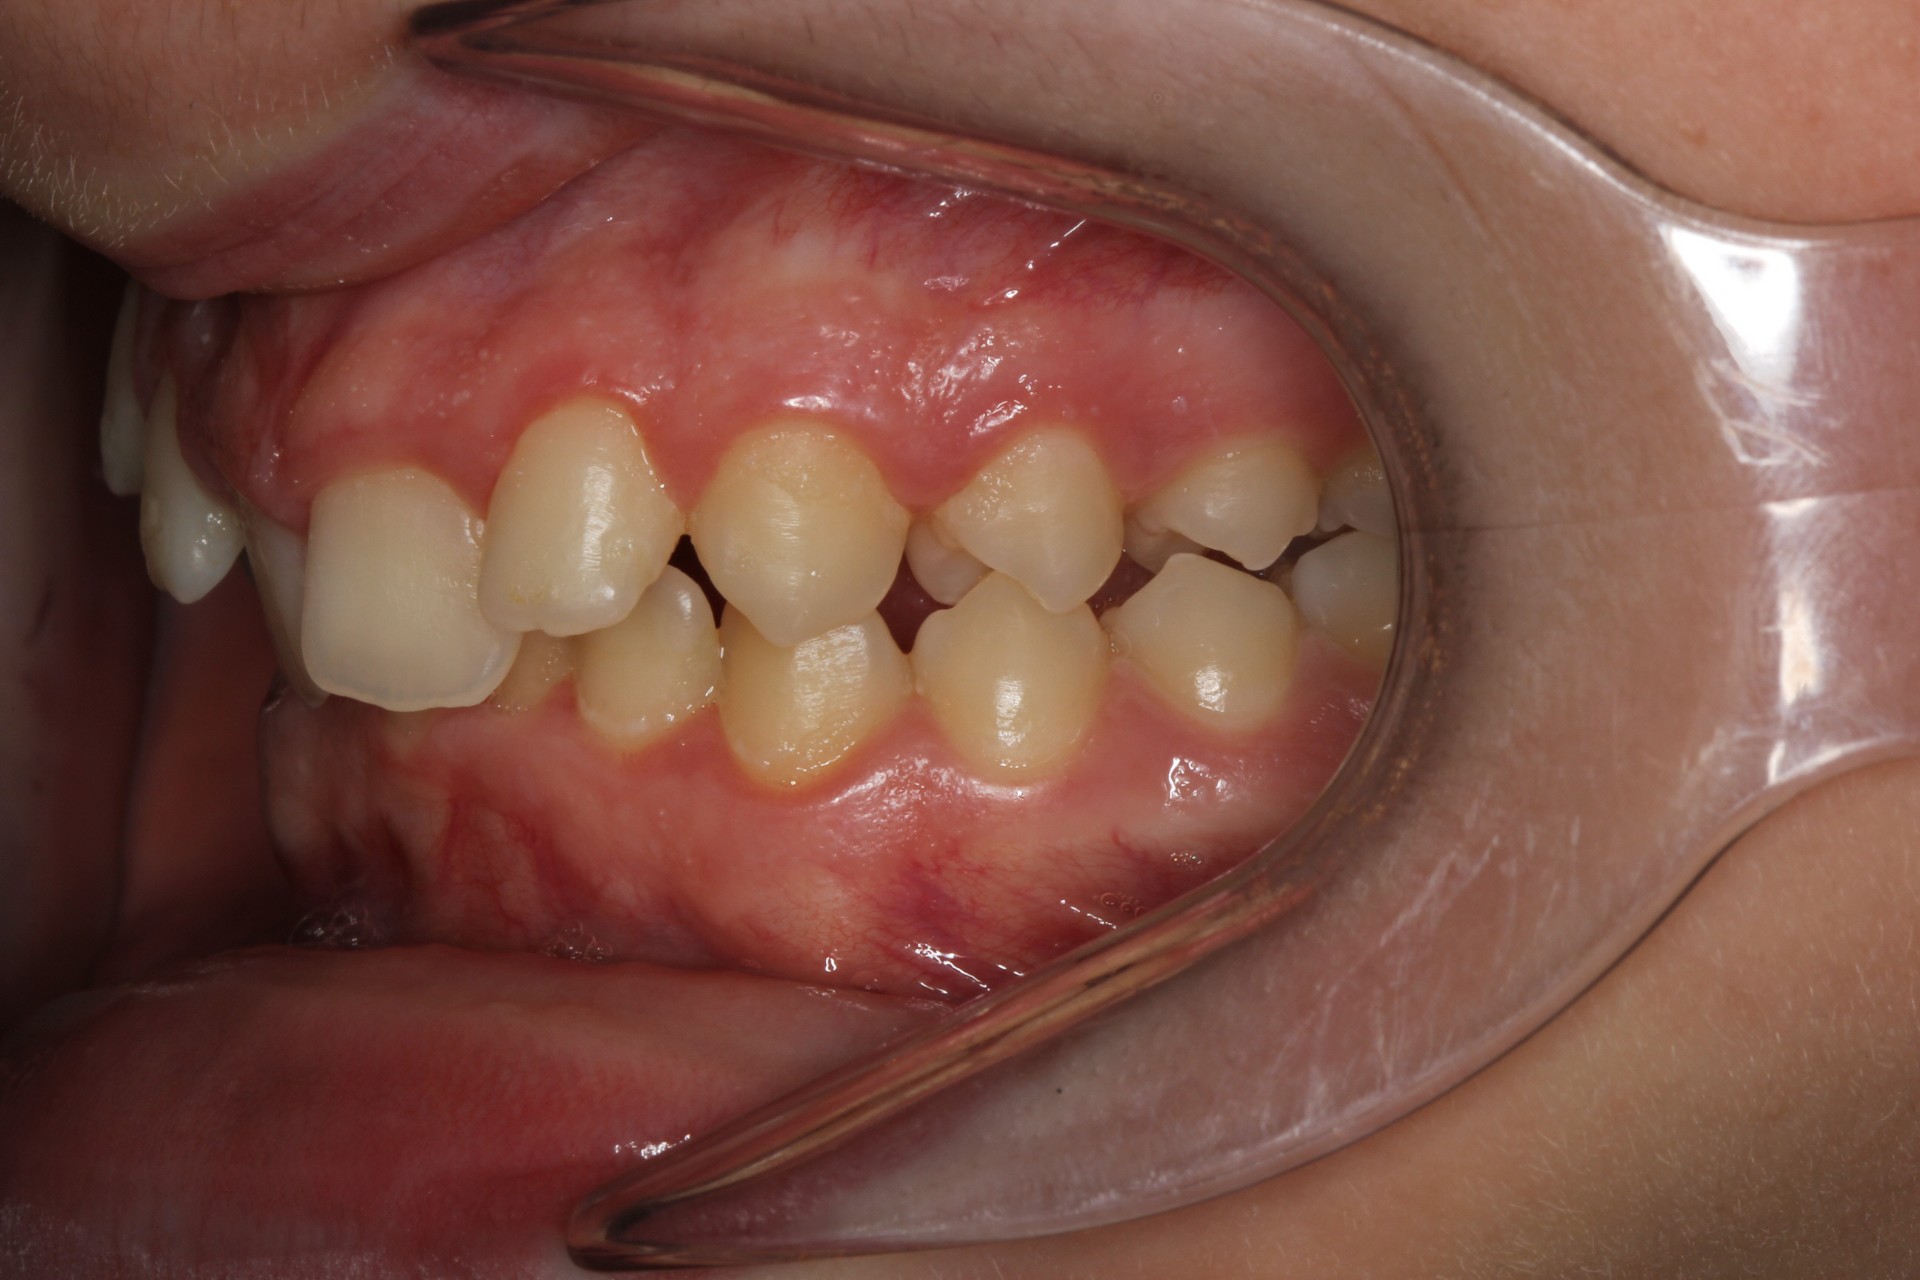

Crowding with lateral open bite – Child case